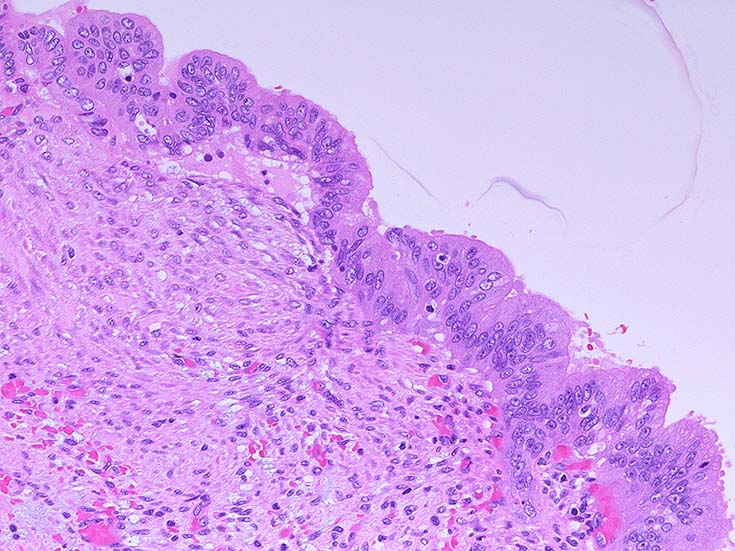

膵上皮内腫瘍性病変 pancreatic intraductal neoplasm(PanIN)*16

Low-grade PanINとhigh-grade PanINの分類

low-grade PanIN

PanINの図譜はJohns Hopkins The Sol Goldman Pancreatic Cancer Research CenterのHome page*19から引用.

1. PanIN-1; PanIN発生の初期段階. 組織学的に, 核異型を伴わない, 核の極性が保たれている.